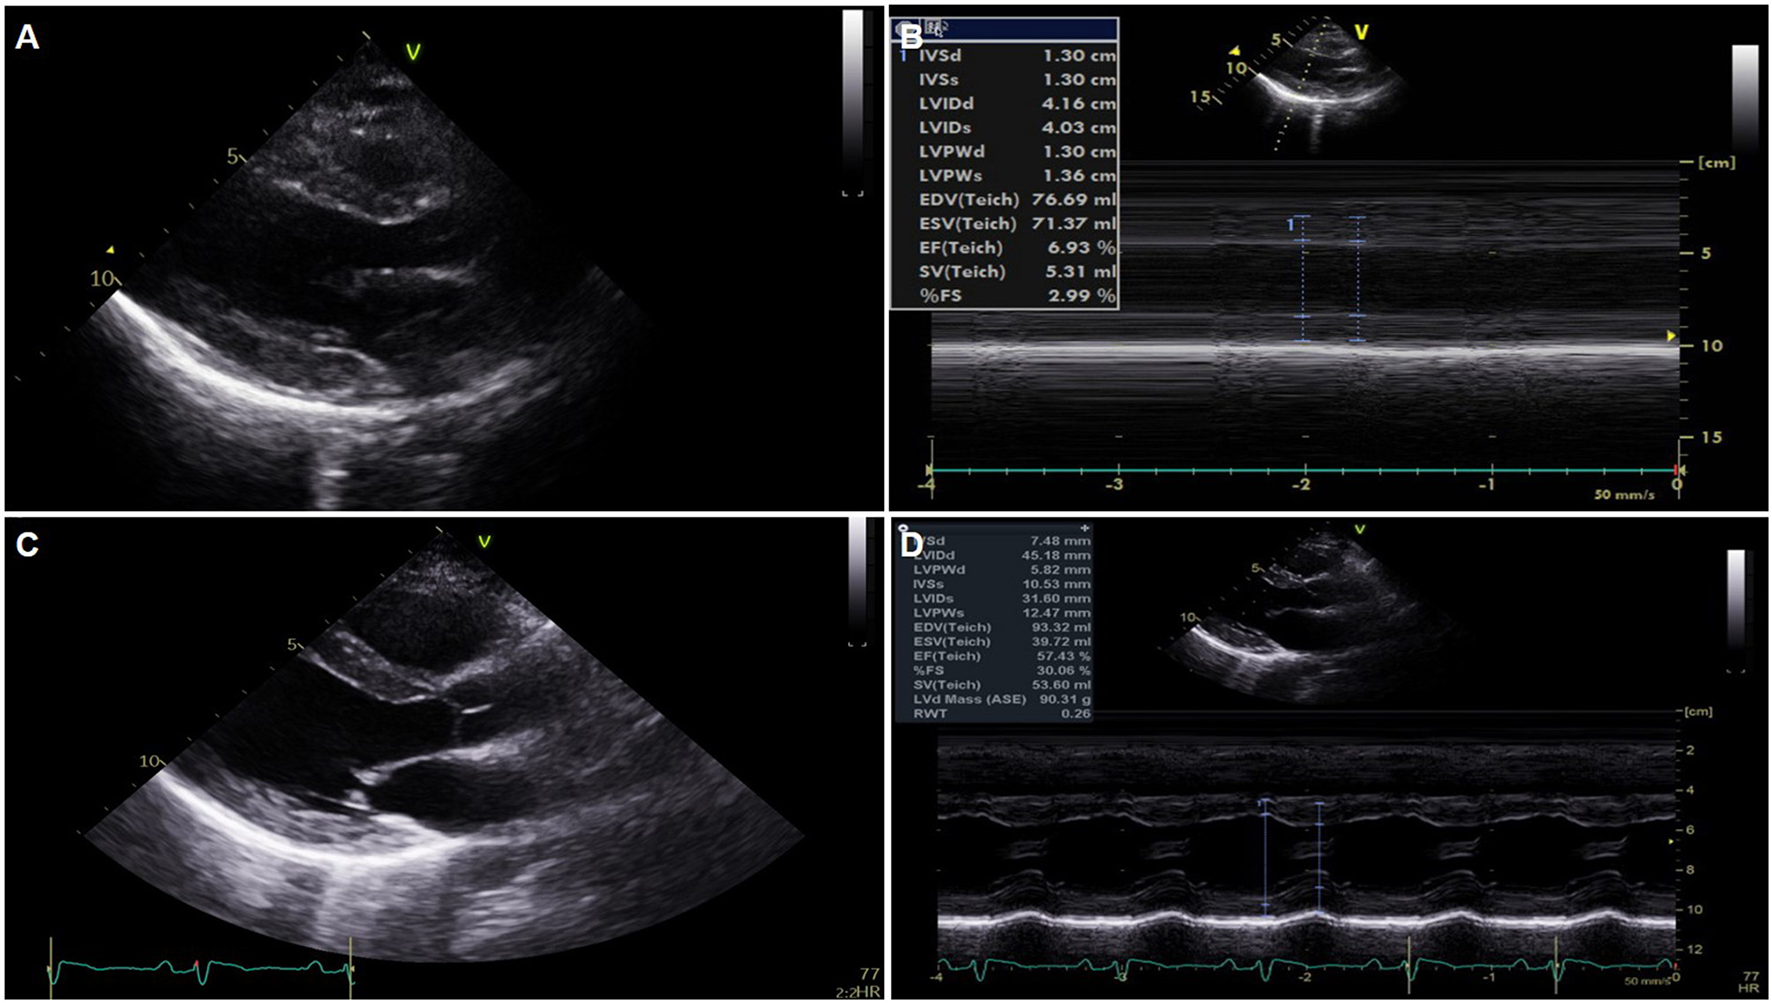

Figure 2

Serial changes of echocardiography. (A,B) Global akinesia with severe left ventricular (LV) dysfunction and marked edematous left ventricular wall thickening on portable echocardiography performed just after extracorporeal membrane oxygenation application. (C,D) Normalized LV function and wall thickness on pre-discharge echocardiography.

A previously healthy 38-year-old female who received the BNT162b2-mRNA vaccine (Pfizer-BioNTech) 7 days ago presented with ongoing chest pain. The patient did not have any underlying disease, significant family history, and was not on other medications. She was transferred to our heart center because of ST segment elevation on electrocardiogram (ECG), and cardiac arrest occurred immediately after arrival at our center. Despite 10 min of cardiopulmonary resuscitation (CPR), recovery of spontaneous circulation was not achieved. With the aid of extracorporeal membrane oxygenation (ECMO), ECPR (23 French drain cannula into the right common femoral vein and 17 French perfusion cannulas into the left common femoral artery, total CPR time-25 min) was applied. The mental state of the patient was recovered, and there were no remarkable abnormal focal neurologic signs. The ECG showed an extensive ST segment elevation with bizarrely wide QRS complexes in the entire precordial and limb leads except for lead aVR (Figure 1A). It eventually progressed into a total ventricular and atrial electrical standstill lasting for more than 2 h (Figure 1B) and returned to the previous ECG pattern thereafter. Portable echocardiography revealed global akinesia with severe left and right ventricular dysfunction (ejection fraction <10% by visual estimation) and marked edematous left ventricular (LV) wall thickening (13 mm) (Figures 2A,B) (Supplementary Videos 1, 2). Additional cannulation through the left common femoral vein into the interatrial septum via atrial septostomy for left heart unloading, coronary angiography, and endomyocardial biopsy (EMB) were done in the catheterization room. There were no stenoses in both the coronary arteries. Laboratory findings showed marked elevation of cardiac troponin I (68.507 ng/ml), N-terminal probrain type natriuretic peptide (32,947 pg/ml), and D-dimer (16.32 mg/L FEU). Fibrinogen assay was normal (205.3 mg/dl). A screening test of severe acute respiratory syndrome coronavirus 2 (SARS-CoV-2) RNA with a polymerase chain reaction was negative, and other viral infection panels and the antibody test to autoimmune disease were non-specific.

On the second hospital day, the follow-up ECG showed a similar extensive ST segment elevation with bizarrely wide QRS complexes, and echocardiography revealed no significant interval change in the previously noted global akinesia with severe biventricular dysfunction.

On the third hospital day, echocardiography showed more improvement in both the ventricular function (ejection fraction: 30%) and the decreasing thickness of the LV wall (10 mm). In addition, the ECG showed a more decreased ST segment elevation with the narrowing of QRS complexes (Figure 1C). The patient was extubated on the same day, and ECMO weaning was done on the sixth day. EMB demonstrated compatible findings of acute lymphocytic myocarditis (Figure 3).

Predischarge ECG revealed the normalization of previously noted ST segment elevation and QRS width, and an increased but low voltage QRS complex that remained (Figure 1D). LV function (ejection fraction: 58%) and wall thickness were normalized on the predischarge echocardiography (Figures 2C,D) (Supplementary Videos 3, 4), and the patient was discharged and followed up at an outpatient clinic without clinical events.